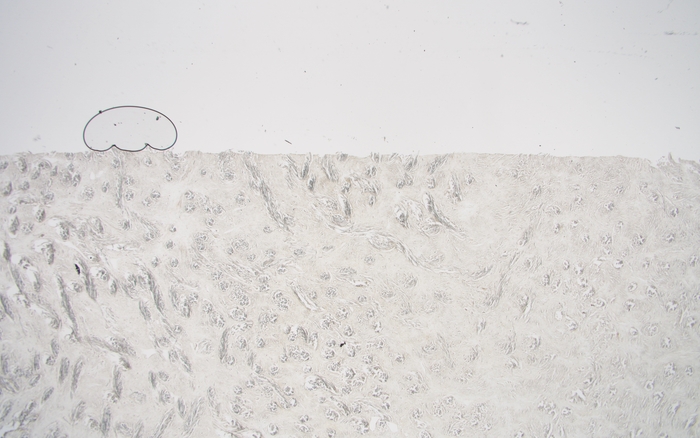

제목: 꼬마자동차 (2019)

조직소견: 거즈육아종

작품설명: 조직절편을 만들면 얇은 유리판으로 덮은 다음 현미경으로 관찰하게 된다. 절편이 두꺼우면 기포가 들어가는 경우가 있다. 이 작품에서는 기포가 마치 절벽 위를 달리는 꼬마자동차처럼 보인다.